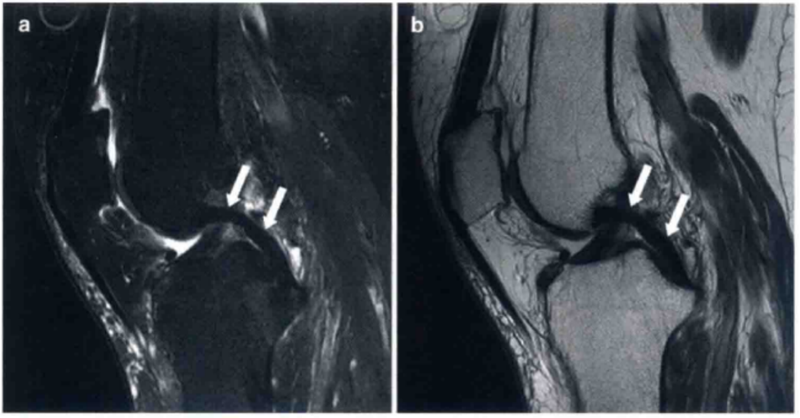

图8 a和b显示在T2和质子加权像上为正常的PCL,可见正常的弧度和在两个序列中为均值低信号

图9 a和b显示的为矢状位质子加权像和T2上PCL损伤的图像(箭头)。PCL变厚、水肿,但不是完全的断裂